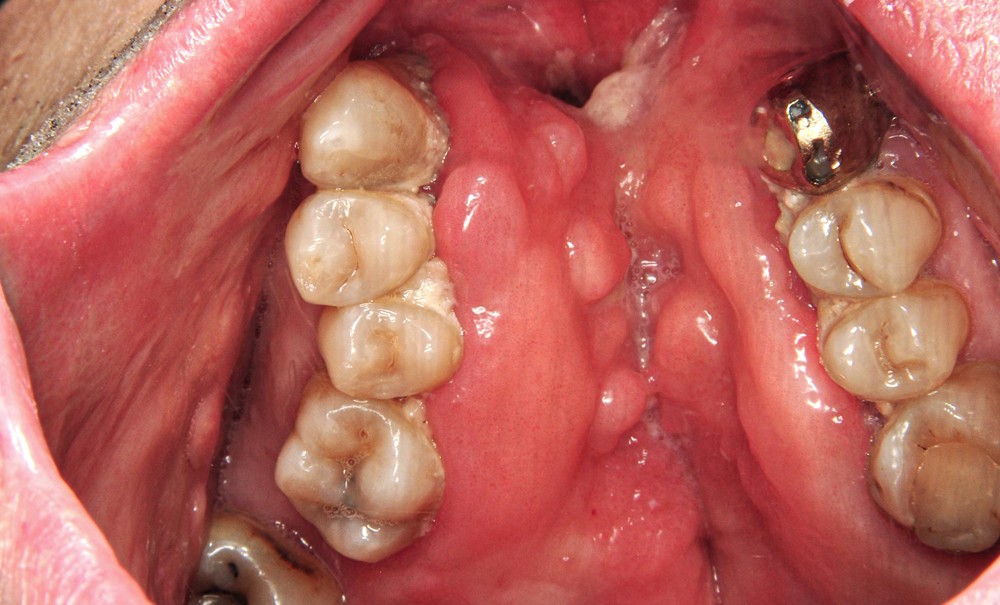

Le cas clinique suivant met en évidence une prise en charge prothétique chez un patient adulte présentant une division palatine séquellaire avec communications bucco-nasales, responsables d’une rhinolalie, et de reflux liquidiens et alimentaires survenant au cours de la mastication. La réhabilitation prothétique a été réalisée au sein de l’unité de prothèse maxillo-faciale du service d’odontologie et de médecine bucco-dentaire du CHU de Toulouse, de septembre 2021 à février 2022.

PRÉSENTATION DU CAS CLINIQUE

Un patient âgé de 52 ans…